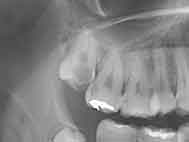

右上 親知らず(淀川区 28才 男性)

治療内容

親知らずの抜歯